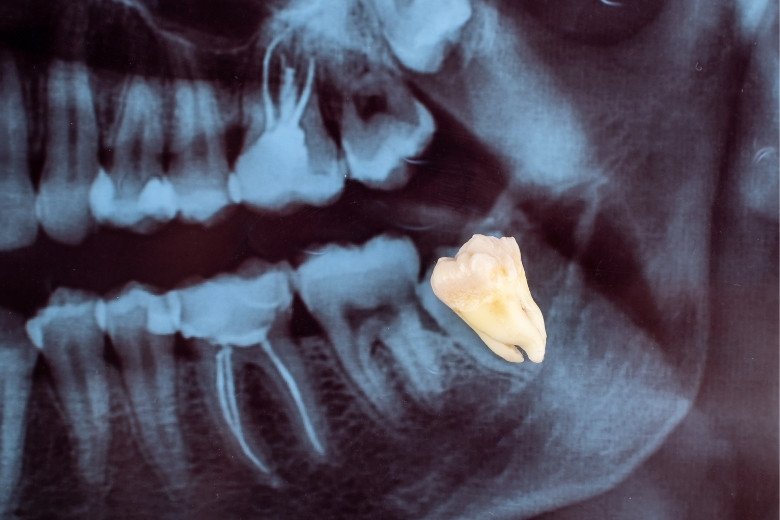

Wisdom tooth extraction is a routine oral surgery procedure designed to remove the third molars, which are commonly known as wisdom teeth. These teeth typically erupt between the ages of 17 and 25, and in many cases, they do not have enough room to emerge properly. When left untreated, problematic wisdom teeth can cause severe pain, swelling, infection, gum disease, tooth decay, or even lead to misalignment of neighboring teeth.

Comprehensive Oral Examination & X-ray Imaging – Detailed evaluation of tooth position and surrounding bone structure.

Surgical Removal of the Tooth – Performed with precision to protect adjacent teeth and tissues.